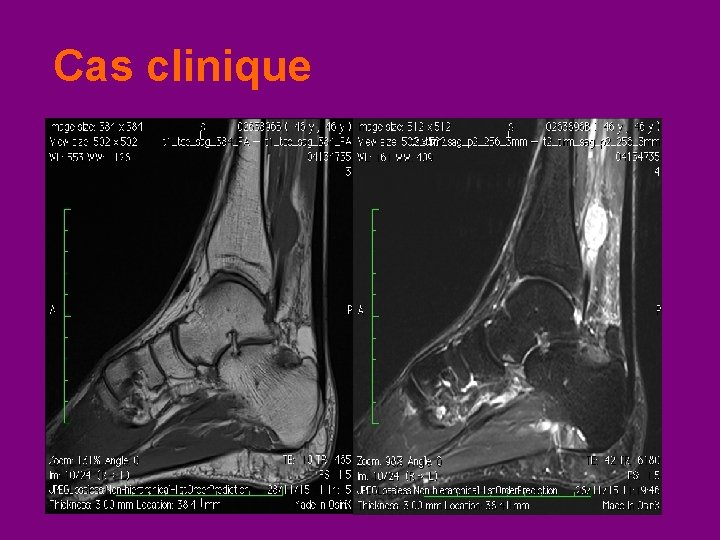

Cas clinique • Depuis > 1 an : douleur audessus de la cheville gauche près du tendon d’Achille • De façon intermittente : décharges électriques irradiées à la plante du pied • Pas de déficit moteur ou sensitif à l’examen clinique

Cas clinique Dr G

Cas clinique